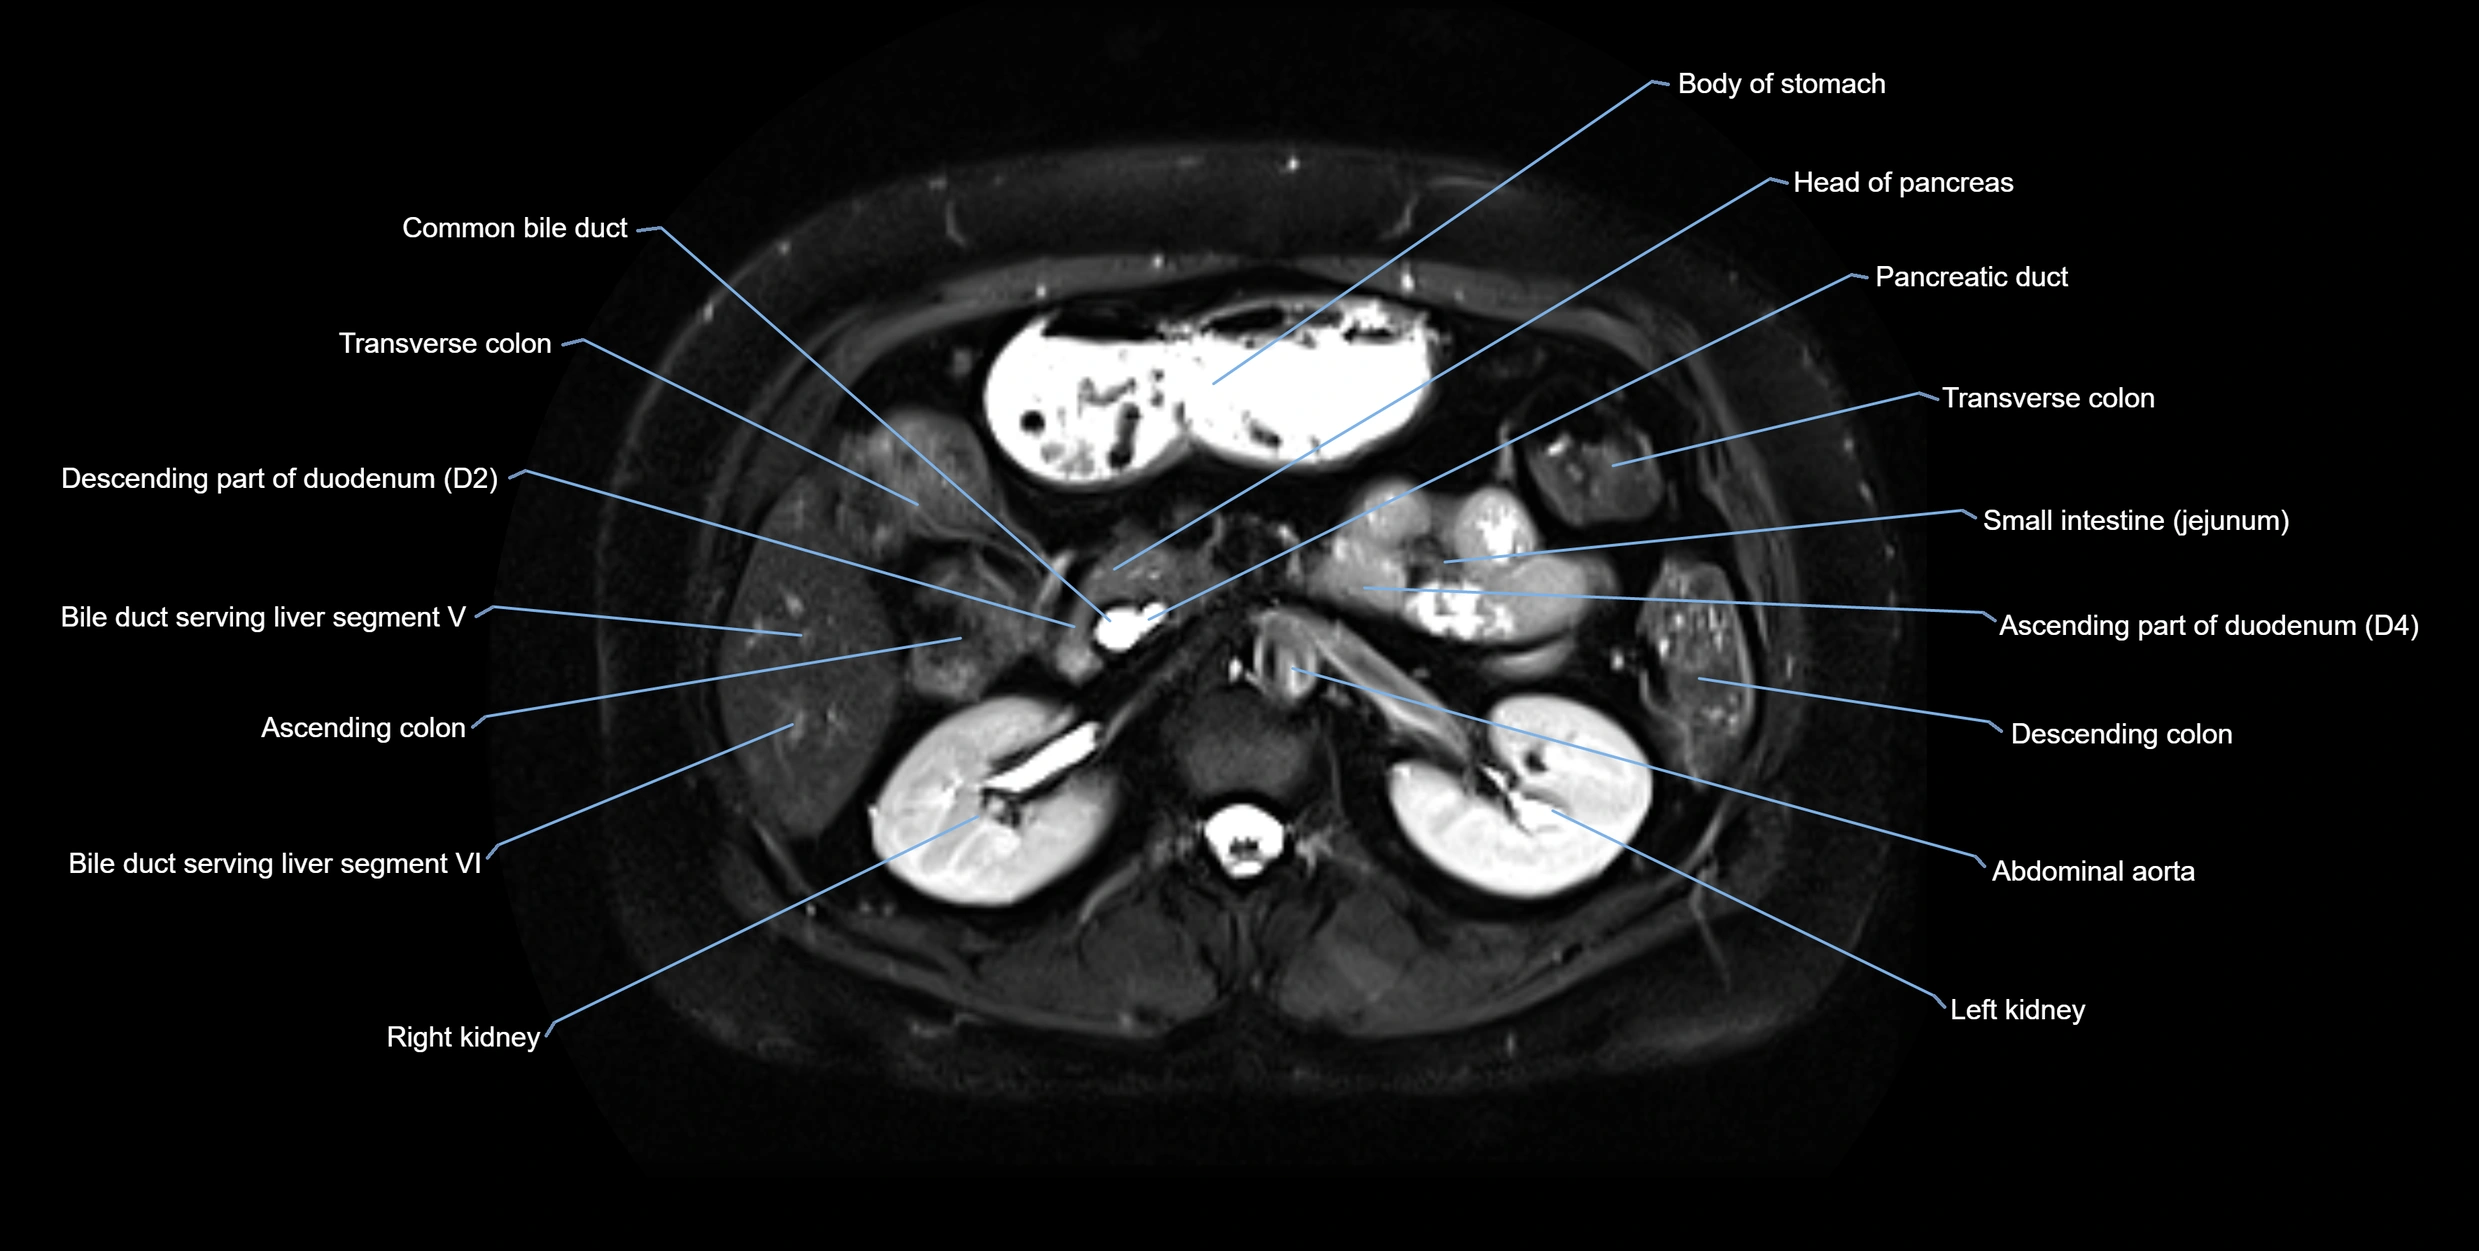

• Anteriorly: Duodenal wall (second part)

• Posteriorly: Head of the pancreas and main pancreatic duct

• Superiorly: Common bile duct

• Inferiorly: Main pancreatic duct (duct of Wirsung) and major papilla

MRI Appearance

T2-weighted images:

• Duct fluid appears bright

• Accessory duct seen as a fine high-signal tubular structure in pancreatic head

MRI image

image

Fullscreen Image